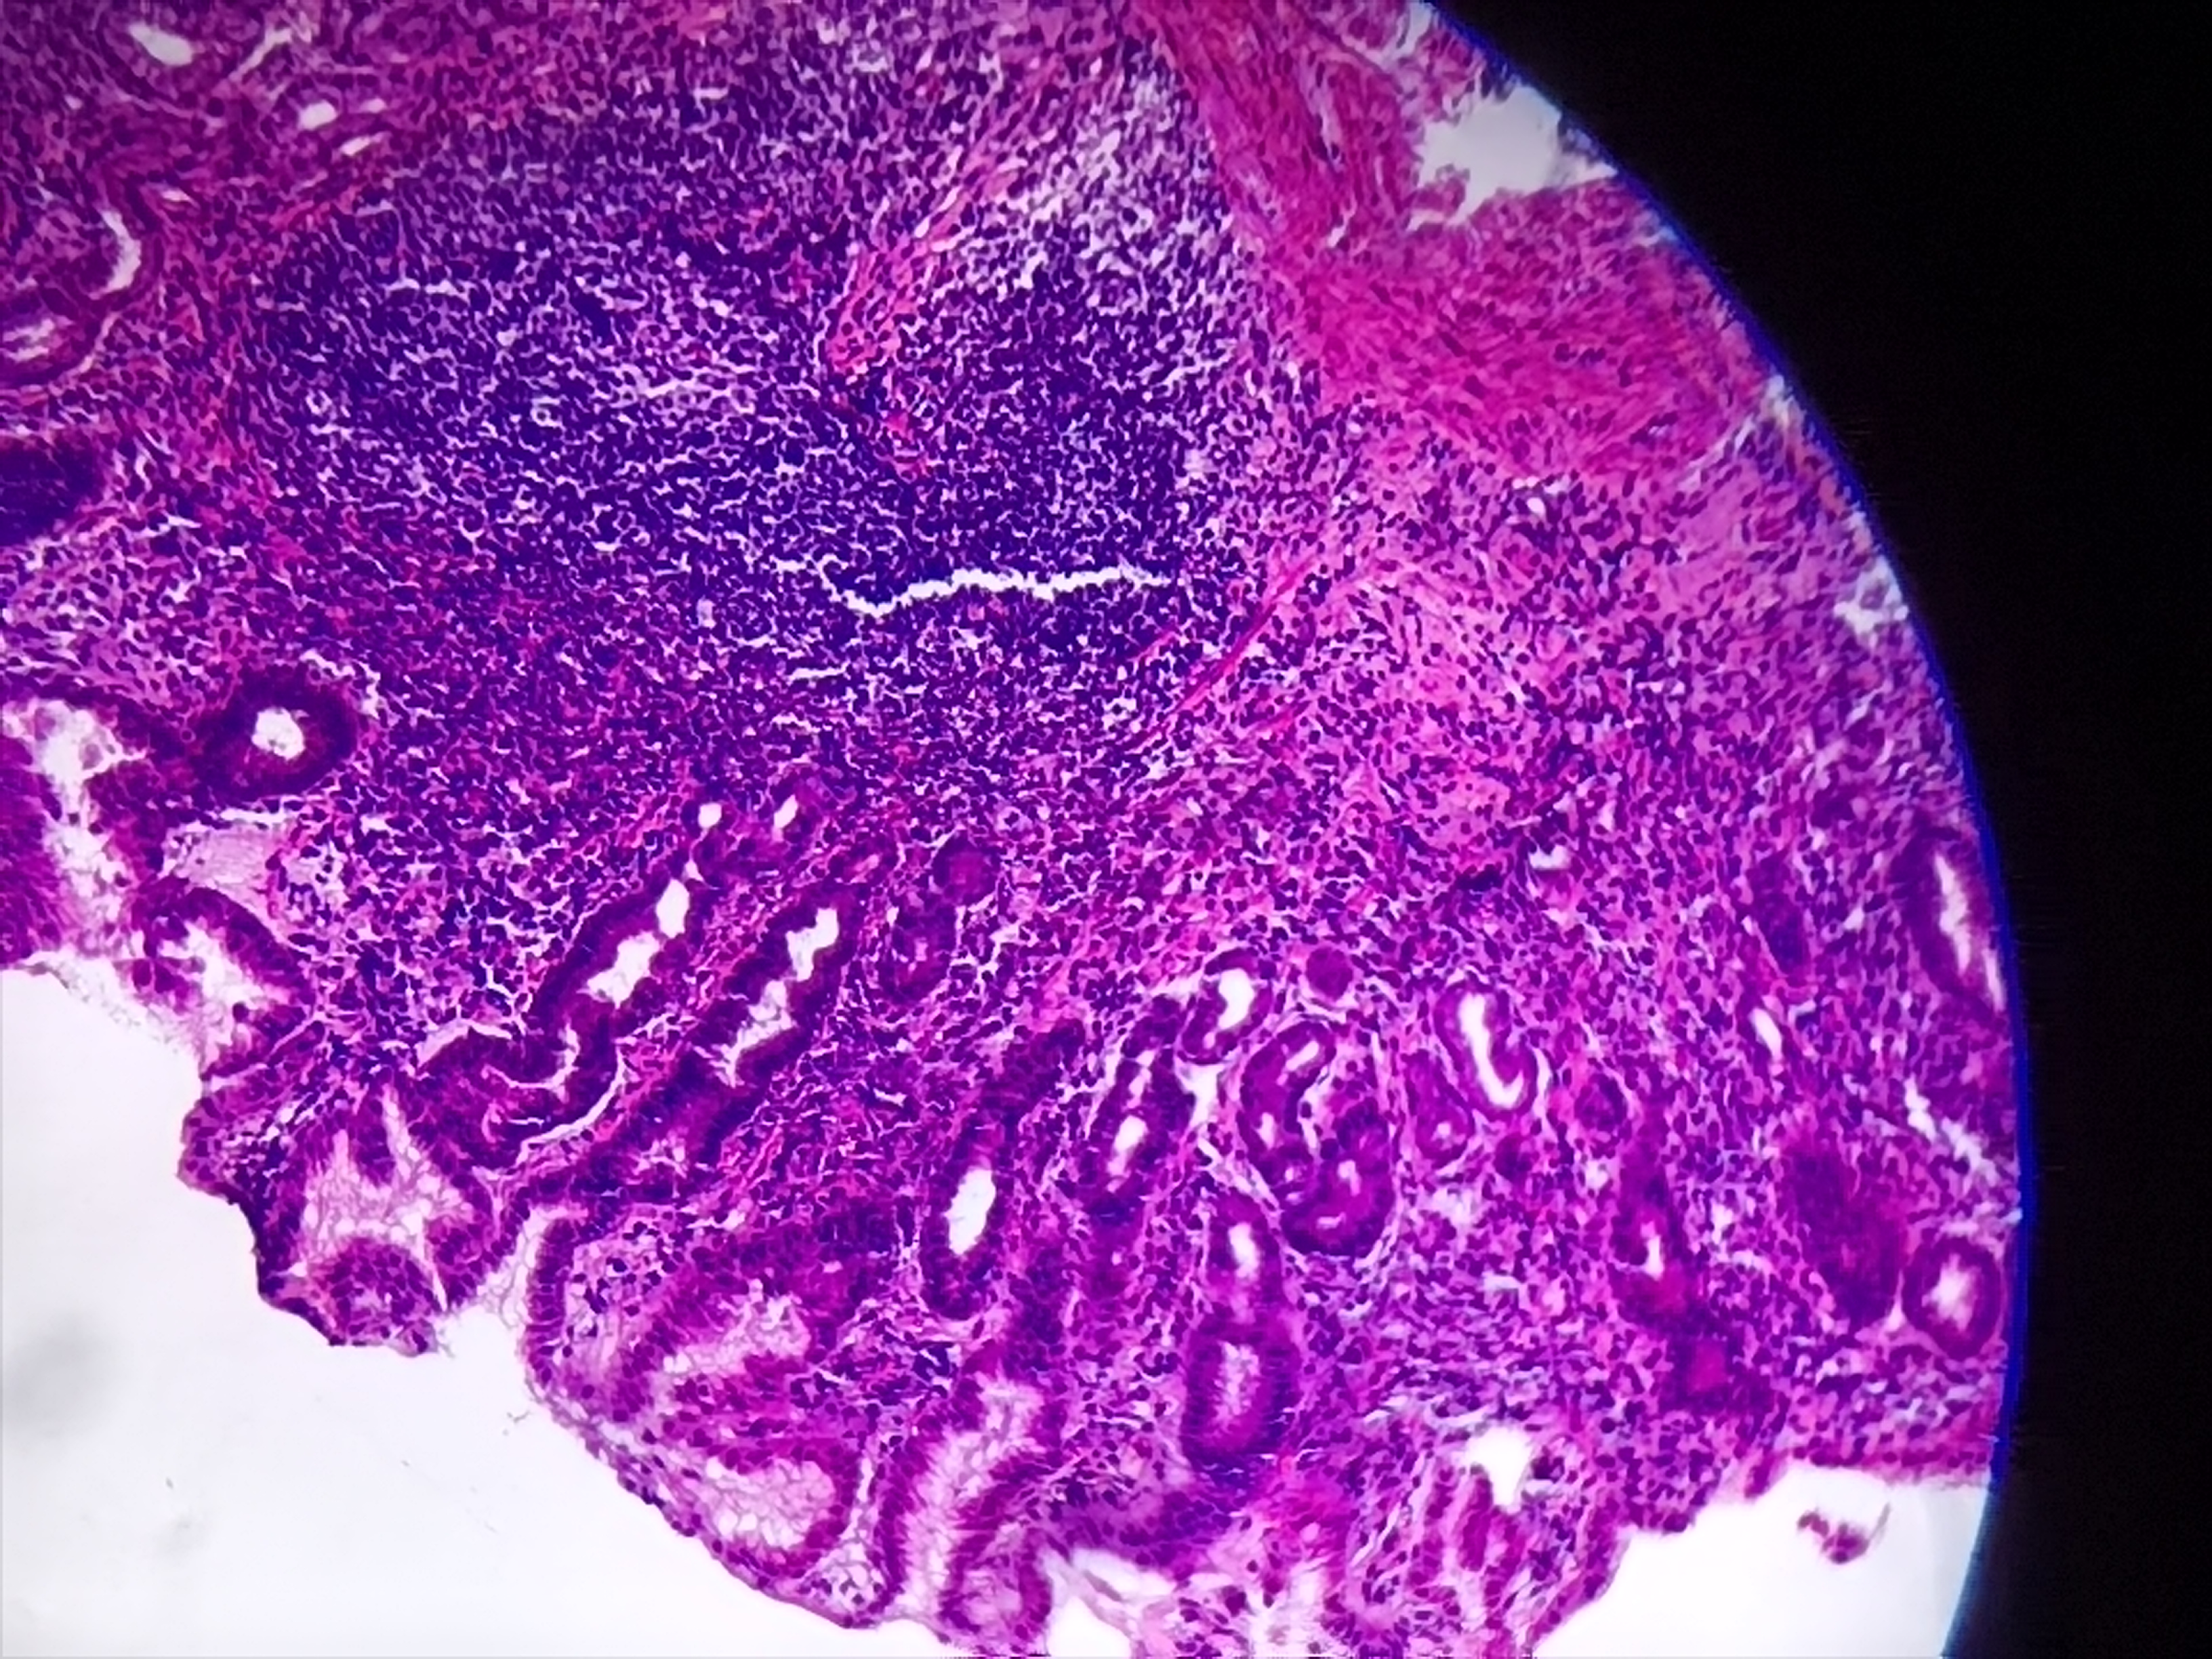

胃窦活检

胃窦部分粘膜表面血痂及少量渗血,多发白苔溃疡

胃窦粘膜活检

灰白色组织1块

良性的,片子质量不好!

考虑慢性活动性炎,图3靠右上方的那一个区域看上去有些模糊, 薄切一张重染再看看。